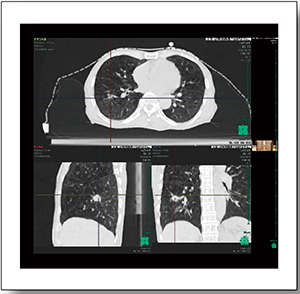

症例1は,76歳,女性。小細胞肺癌(cT3N1M0,右下葉原発)のため化学療法が行われたが,制御不良であったため放射線治療(CBDCA+VP-16併用,60Gy/30回)が施行された。はじめに4D-CTにてITVを決定するが,4D-CTから得られる呼気相と吸気相の画像をPET画像とフュージョンすると,全相においてほぼ一致していることが認められる(図4)。ITVはすでに決定しているので,これを基にPTVを設定すれば,動きのある領域の腫瘍であっても,きわめて高精度な照射が可能となる。図5は実際の治療計画である。肺がんの場合,主腫瘍とリンパ節転移は呼吸による動きが異なるが,4D-CT画像を用い,それぞれに最適なフィールド設定が可能であり,適切な照射が可能となる。本症例は,治療1か月後の画像にて著明な腫瘍縮小が認められた。

図4 症例1:4D-CTから得られる呼気相・吸気相の画像およびPETとのフュージョン画像